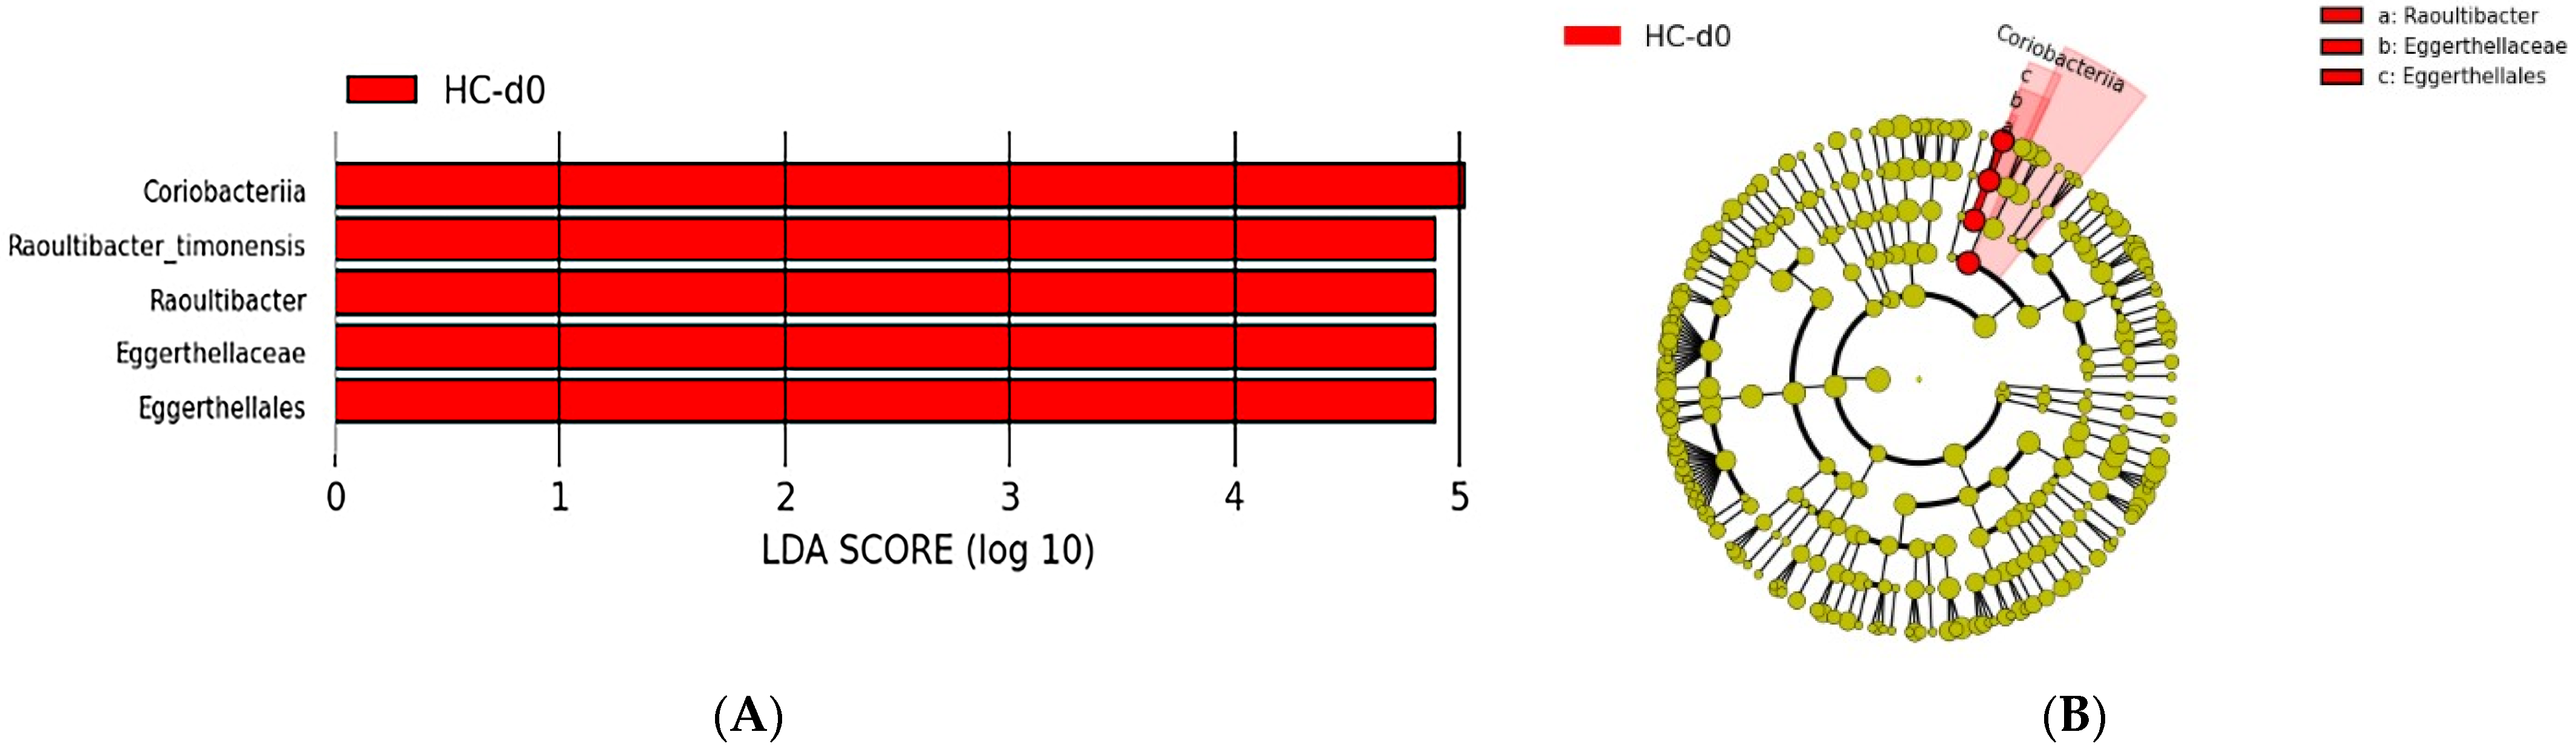

Taxonomic Analysis of the Intestinal Microbiota Composition at D0 in the Two Cat Populations

Biodiversity of the Fecal Microbiota in the Two Cat Populations

4.1.3. Beta Diversity